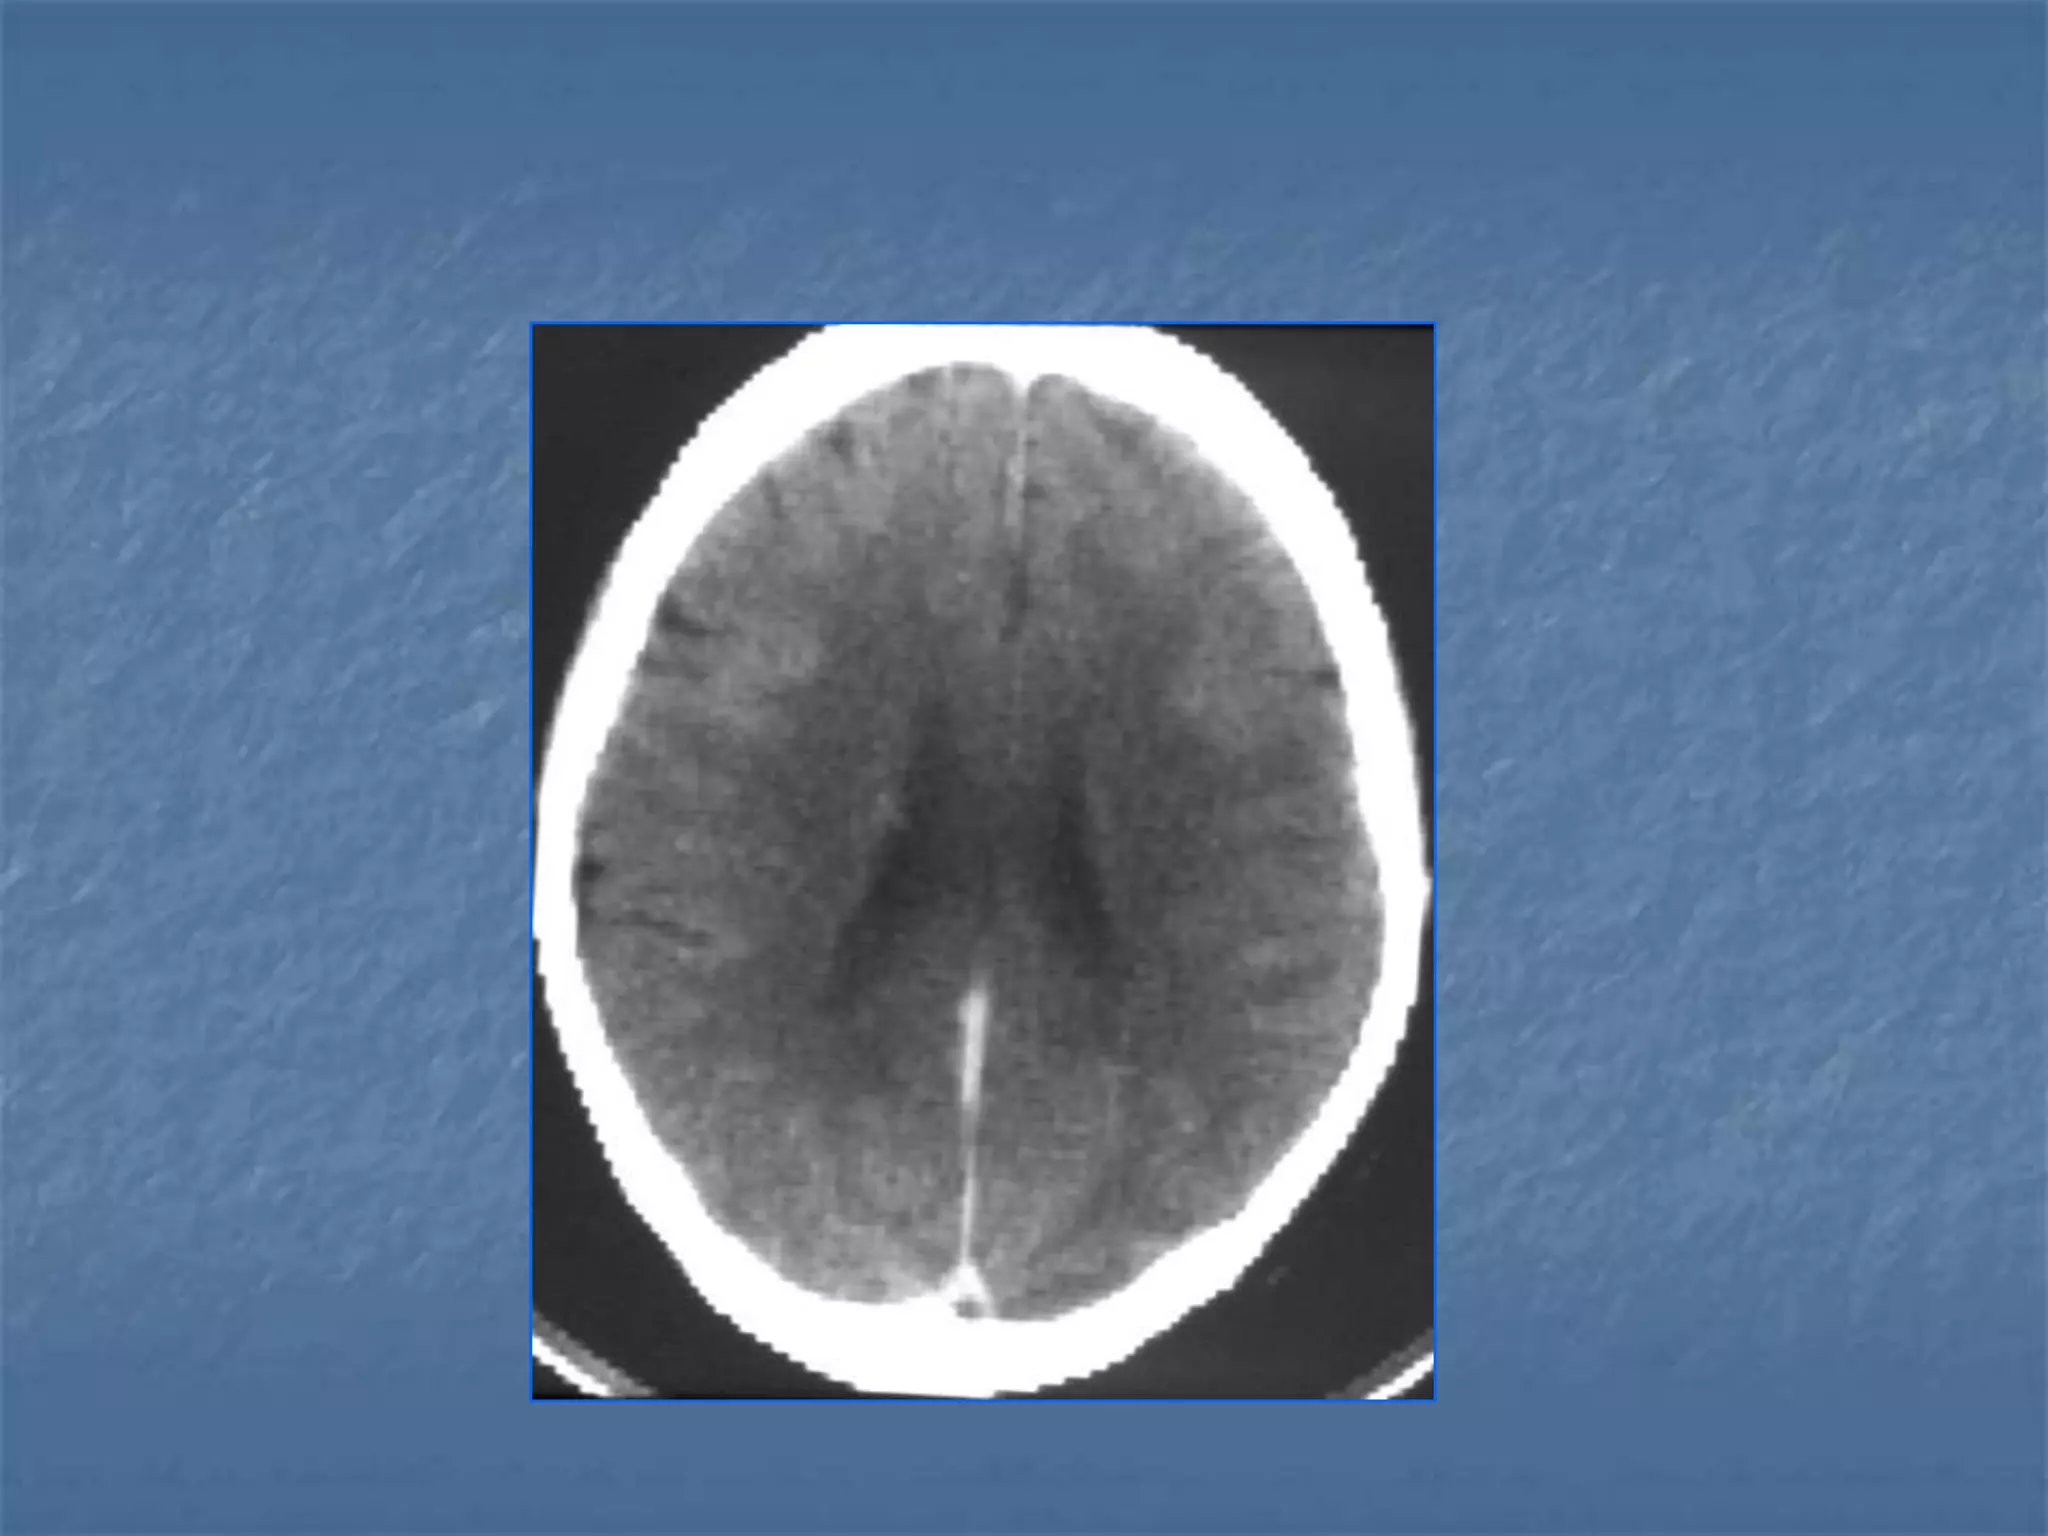

Normal in 50% of ischemic strokes < 6

hrs

CT in Hyperacute Stroke ( 0-6 hrs )

 Not v.sensitive for infarction

 Sensitive for a/c hemorrhage & gross

lesions precluding thrombolytic therapy

20 % within 2 hrs

82 % within 6 hrs

Neuroradiology.1996

Jan;38(1):31-33